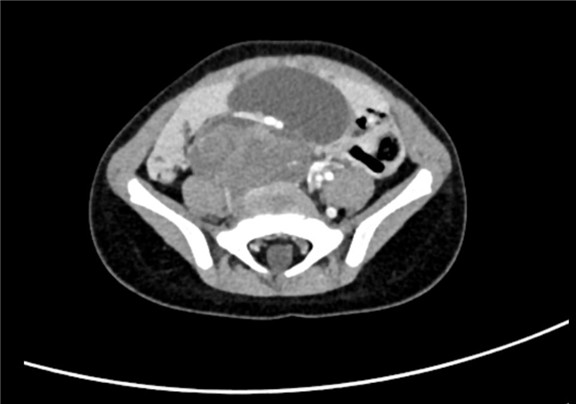

2017-7-4 腹部CT平扫 下腹部及盆腔占位性病变大小约5.4*4.2*4.5cm。

术前CT检查:

动脉期

静脉期